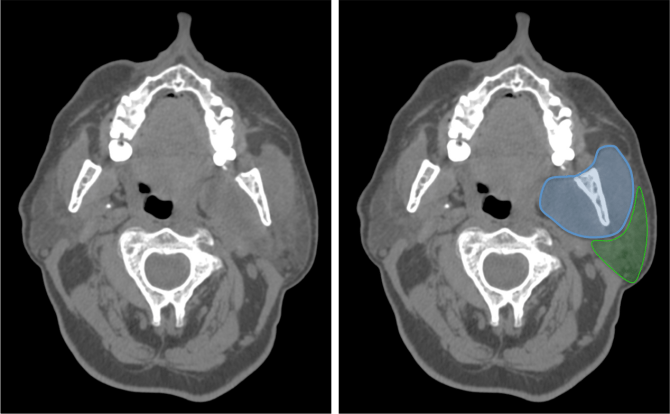

ESPACIO PARAFARÍNGEO.

En este espacio importante donde encontraremos mucosa y tejido linfático. Esta región puede ser el foco de origen de procesos infecciosos como faringitis, amigdalitis y/o abscesos.

Amarillo: mucosa faringea/amígdala.

Rojo: espacio vascular.

Azul: espacio masticador.

Verde: espacio parotídeo.